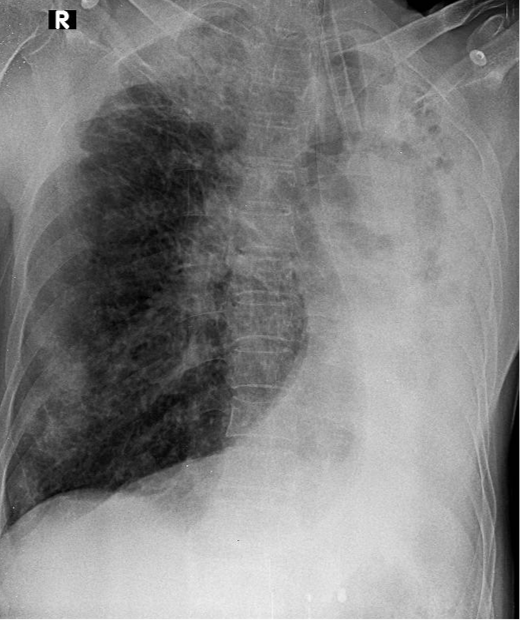

1-Khí quản lệch (T) 2-Có ống thông nội khí quản 3-Thâm nhiểm phế nang + khí phể thũng rải rác phổi (P) => Viêm phổi (P) 4-Viêm phổi + xẹp phổi (T), kéo bóng tim và trung thất lệch(T)